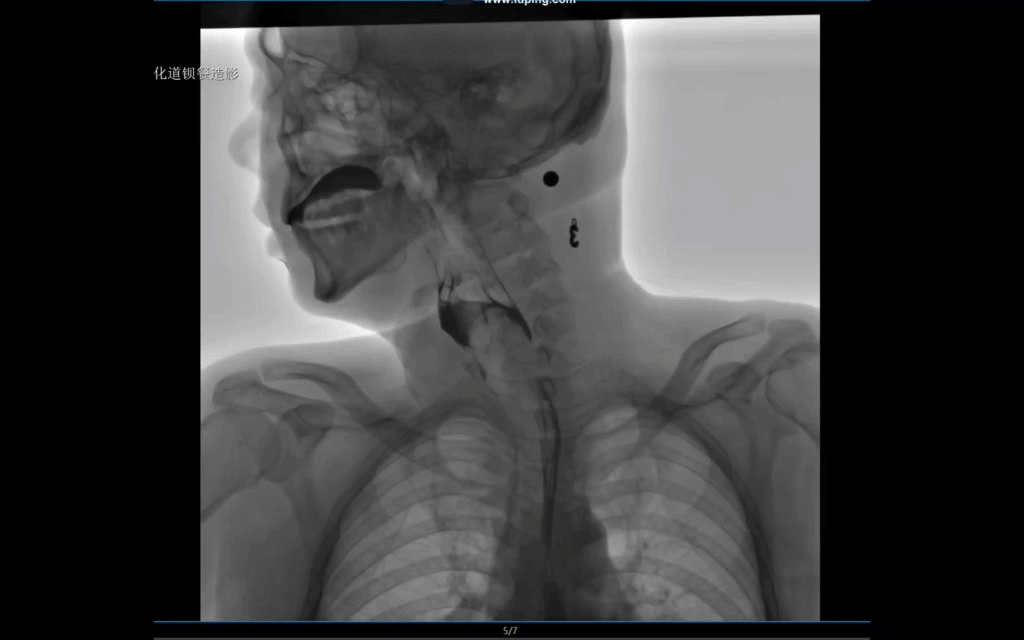

采用新一代動態(tài)平板探測器,兼具動靜態(tài)采集功能,輕松實現(xiàn)數(shù)字攝影、數(shù)字胃腸、數(shù)字透視、數(shù)字造影、實時高清點片、視頻保存和回放等功能,滿足多科室臨床檢查需求。

17×17英寸大幅面成像,一次曝光即可實現(xiàn)胸部、腹部全覆蓋,無需移動即可觀察整個動態(tài)過程,避免拖尾、噪聲對圖像的影響,避免漏診誤診;最高30幀/s采集幀率,動態(tài)影像更流暢,便于使醫(yī)生觀察細微病變,提高診斷的準確性。